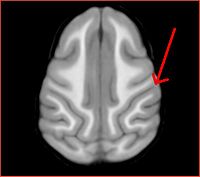

Gucci axial slice (#94) showing contrast for thalamus, globus pallidus, putamen

Same slice, template averaged from registered images